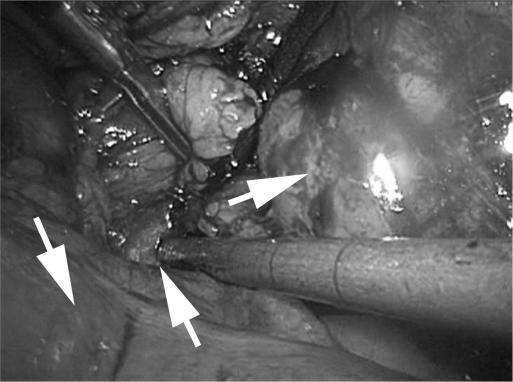

The procedure was performed successfully without complications and with minimal blood loss. The case was marked both by difficulty in mobilizing the sigmoid colon and the limited working space of the pelvis, which made localization of the numerous hilar vessels challenging.

Laparoscopic radical nephrectomy for a pelvic ectopic kidney appears to be safe and efficacious. Success is dependent on familiarity with pelvic anatomy, optimal port placement, and preprocedure knowledge of the often-complicated vascular anatomy of the ectopic kidney. Preoperative imaging to delineate anomalous vascular anatomy is mandatory, and ureteral catheter placement is helpful for intraoperative identification purposes.